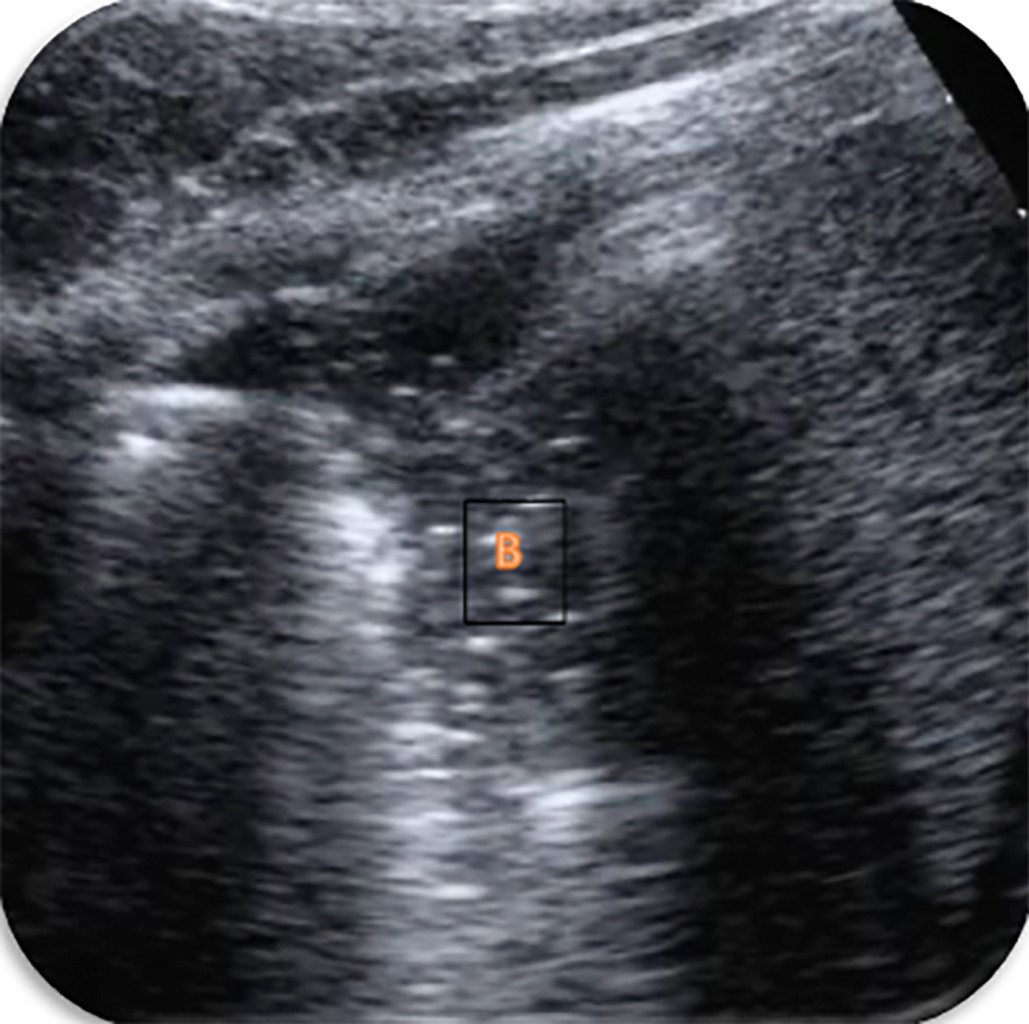

CONSOLIDACIÓN PULMONAR

La consolidación pulmonar hace referencia a la pérdida de una región de pulmón aireado (neumonía, contusión pulmonar, infarto pulmonar, atelectasia). La única condición para que esta consolidación sea observable por ecografía es que se localice a nivel subpleural (90% de las consolidaciones). Los espacios aéreos aparecerán rellenos de líquido o células inflamatorias, por lo que el pulmón se convierte en una masa con buena transmisión sónica. Ecográficamente hay multitud de formas de ver una consolidación. Las más características son(19):

• 1. Signo del pseudotejido: se observa el pulmón con una ecogenicidad similar al hígado/bazo.

• 2. Broncograma aéreo: zona subpleural hipoecogénica con imágenes hiperecogénicas en su interior (aire atrapado) (Figura 6).

• 3. Broncograma líquido: zona subpleural hipoecogénica, con imágenes de contenido hipoecogénico y paredes hiperecogénicas en su interior (líquido atrapado).

Evidentemente hay una gran variedad de patologías (atelectasias, neumonías, neoplasias…) que pueden producir consolidaciones pulmonares, por lo que la correlación de los hallazgos clínicos y ecográficos es fundamental.